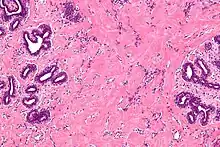

| High magnification micrograph of pseudoangiomatous stromal hyperplasia showing the characteristic small, anastomosing blood vessel-like channels. H&E stain. | |